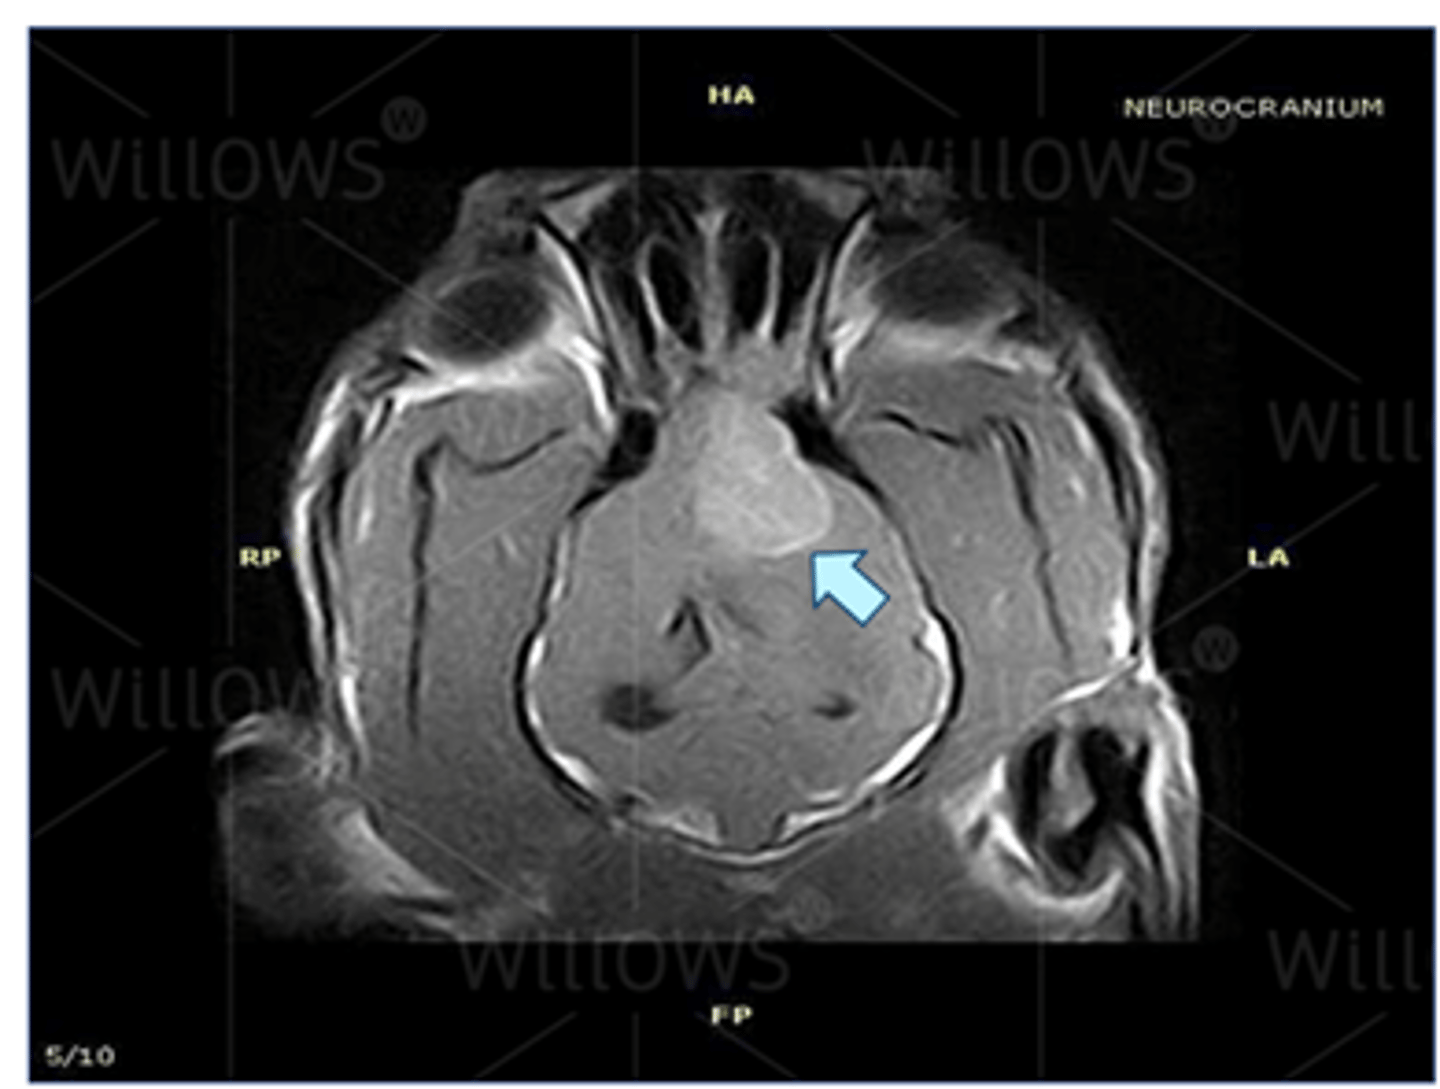

MRI – brain tumour (dog)